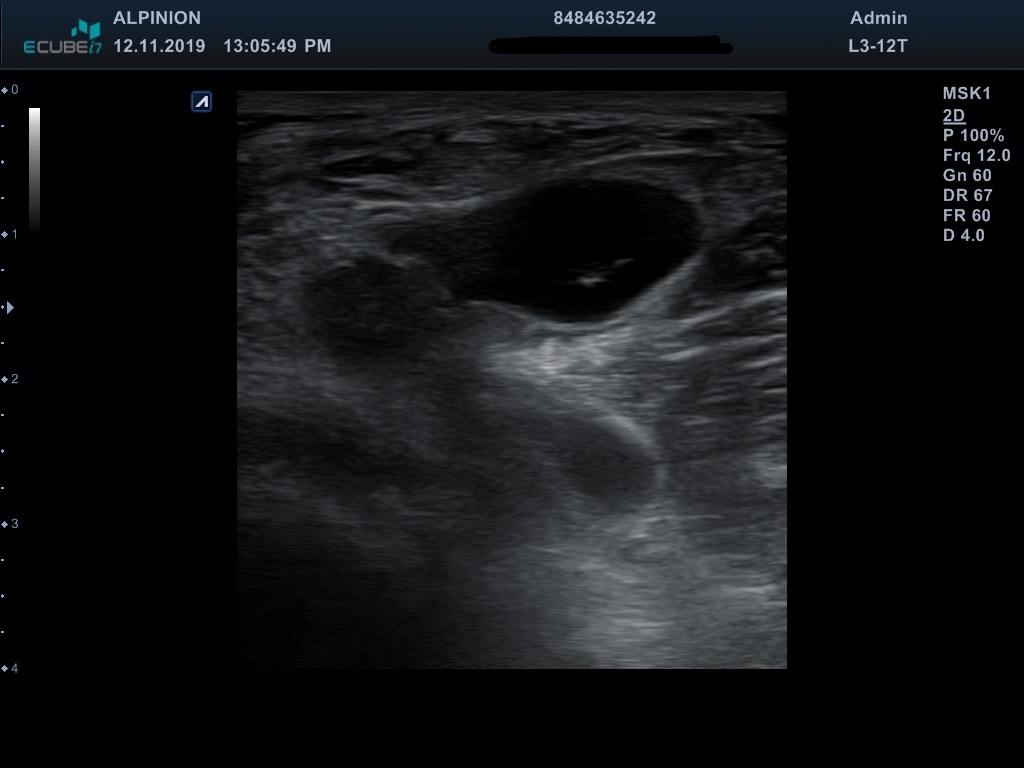

Κύστη Baker

H κύστη Baker ή ιγνιακή κύστη είναι συλλογή υγρού στον ιγνιακό βόθρο.Προκύπτει από επικοινωνία της άρθρωσης του γόνατος με τον θύλακο του ημιυμενώδους-γαστροκνήμιου μυός.

Συνήθως προβάλει ανάμεσα στον τένοντα του υμιυμενώδους μυός και σε αυτόν της έσω κεφαλής του γαστοκνημίου. Βρίσκεται στην οπίσθια και έσω περιοχή του γόνατος σχετικά μακριά από τα ιγνιακά αγγεία.

Η απεικόνισή τους γίνεται μέσω υπερήχου ή μαγνητικής τομογραφίας. Η παρακέντηση της κύστης μπορεί να γίνει εύκολα με καθοδήγηση υπερήχου και αποτελεί οριστική ή προσωρινή θεραπεία. Η αντιμετώπιση είναι κατά κανόνα συντηρητική και σπάνια απαιτείται χειρουργική επέμβαση

Ημιυμενώδης μυς (semitendinosus)

Έσω κεφαλή γαστροκνημίου μυός (gastrocnemius)